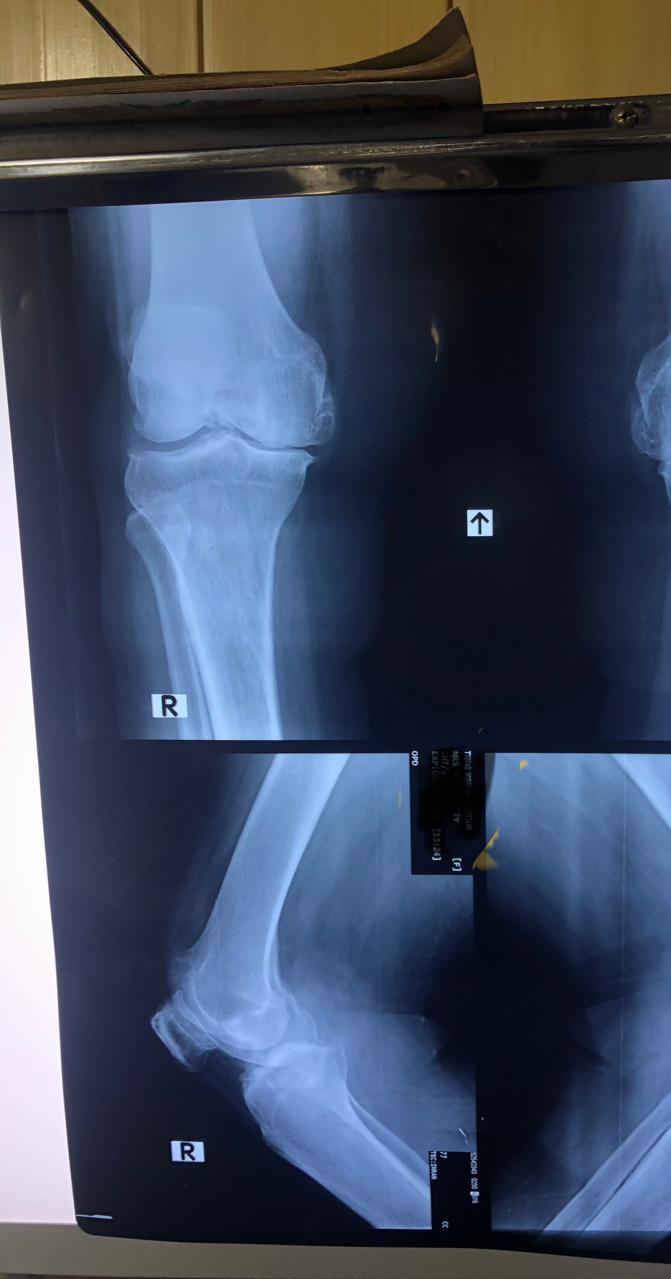

Joint replacement surgery is offered for patients suffering from severe joint pain, stiffness, and reduced mobility due to degenerative joint conditions. The goal of joint replacement is to relieve pain, restore movement, and improve overall quality of life through modern surgical techniques and structured post-operative care.

Total knee and total hip replacement surgeries are performed for advanced joint damage where conservative treatment is no longer effective. These procedures help restore joint function, reduce chronic pain, and allow patients to return to daily activities with improved mobility and comfort.